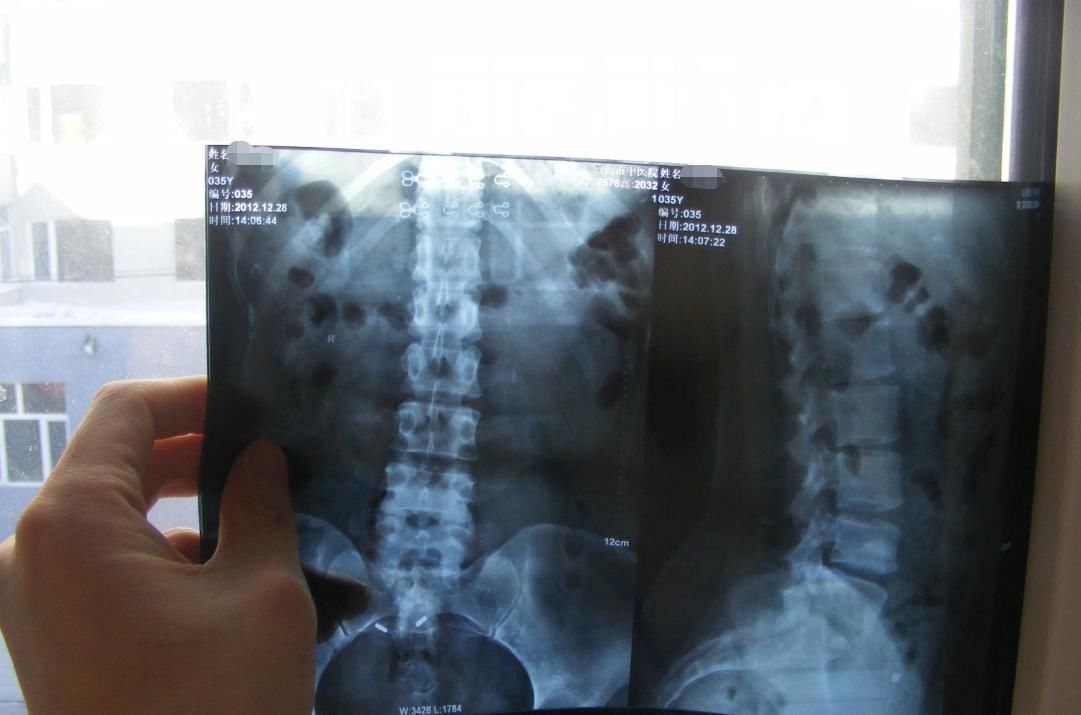

鲁女士 42岁 江苏人

2000年曾因腰间盘突出行外科手术,术后缓解了半年,而后又作,从2014年8月后加重,10月因为腰痛来我所治疗。一共经过两个疗程(六次)韩积霖中药治疗,症状消失,活动自如,又可以正常的劳作了。

再说2012年的这次。

李先生,2012年2月因为劳累又出现左侧臀部疼痛又来找韩及林诊治。患者来前,曾经痛苦难耐,到当地医院诊治,核磁检查:1.腰4/5椎间盘左后突出;2.腰椎退行性变。(见下图),医院建议手术治疗。因不愿第二次手术,再次来所寻求保守治疗。